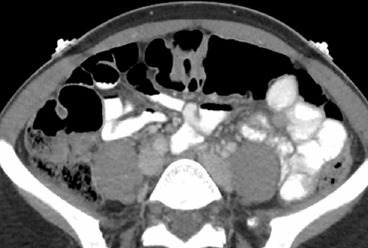

КТ в разных проекциях показывает опухоль в левой почке (стрелка)

Органы брюшной полости, ретроперитонеального пространства. КТ живота является точным методом для диагностики абдоминальных патологий:

опухолей (КТ показывает стадию и распространенность рака, ответ на лечение).